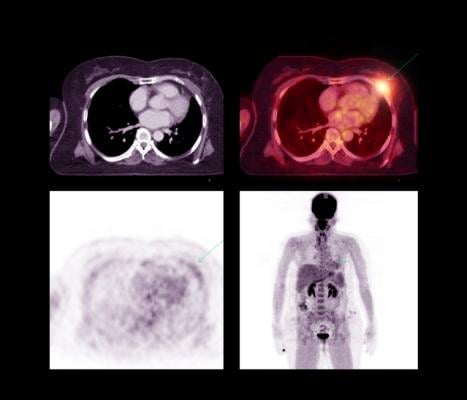

April 11, 2022 — Radiation to the heart during treatment for locally advanced lung cancer is associated with an increased risk of major adverse cardiac events within the first two years following treatment. The higher the cardiac dose exposure, the higher the risk of a cardiac event.

A team at the University of Michigan Health Rogel Cancer Center, in partnership with the statewide Michigan Radiation Oncology Quality Consortium (MROQC) lung cancer collaborative, co-led by Shruti Jolly, M.D., and Peter Paximadis, M.D., of Spectrum Health Lakeland in St. Joseph, Michigan, found that raising awareness about the risk of radiation exposure to the heart and standardizing cardiac exposure limits reduced the average dose to the heart by 15% and reduced the number of patients receiving the highest heart doses by half without minimizing tumor treatment or increasing dosage to other at-risk organs in the chest.